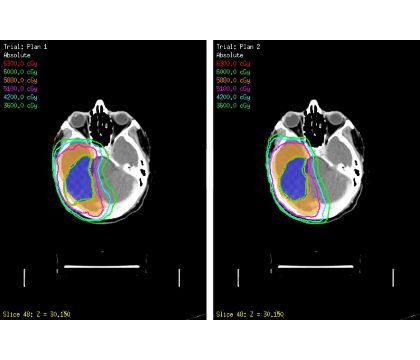

Generate high quality plans on the first pass

The Auto-Planning engine optimizes target coverage and OAR sparing. It reduces the need for multiple plan reviews with the physician and physicist, and runs in the background leaving time free for other tasks.